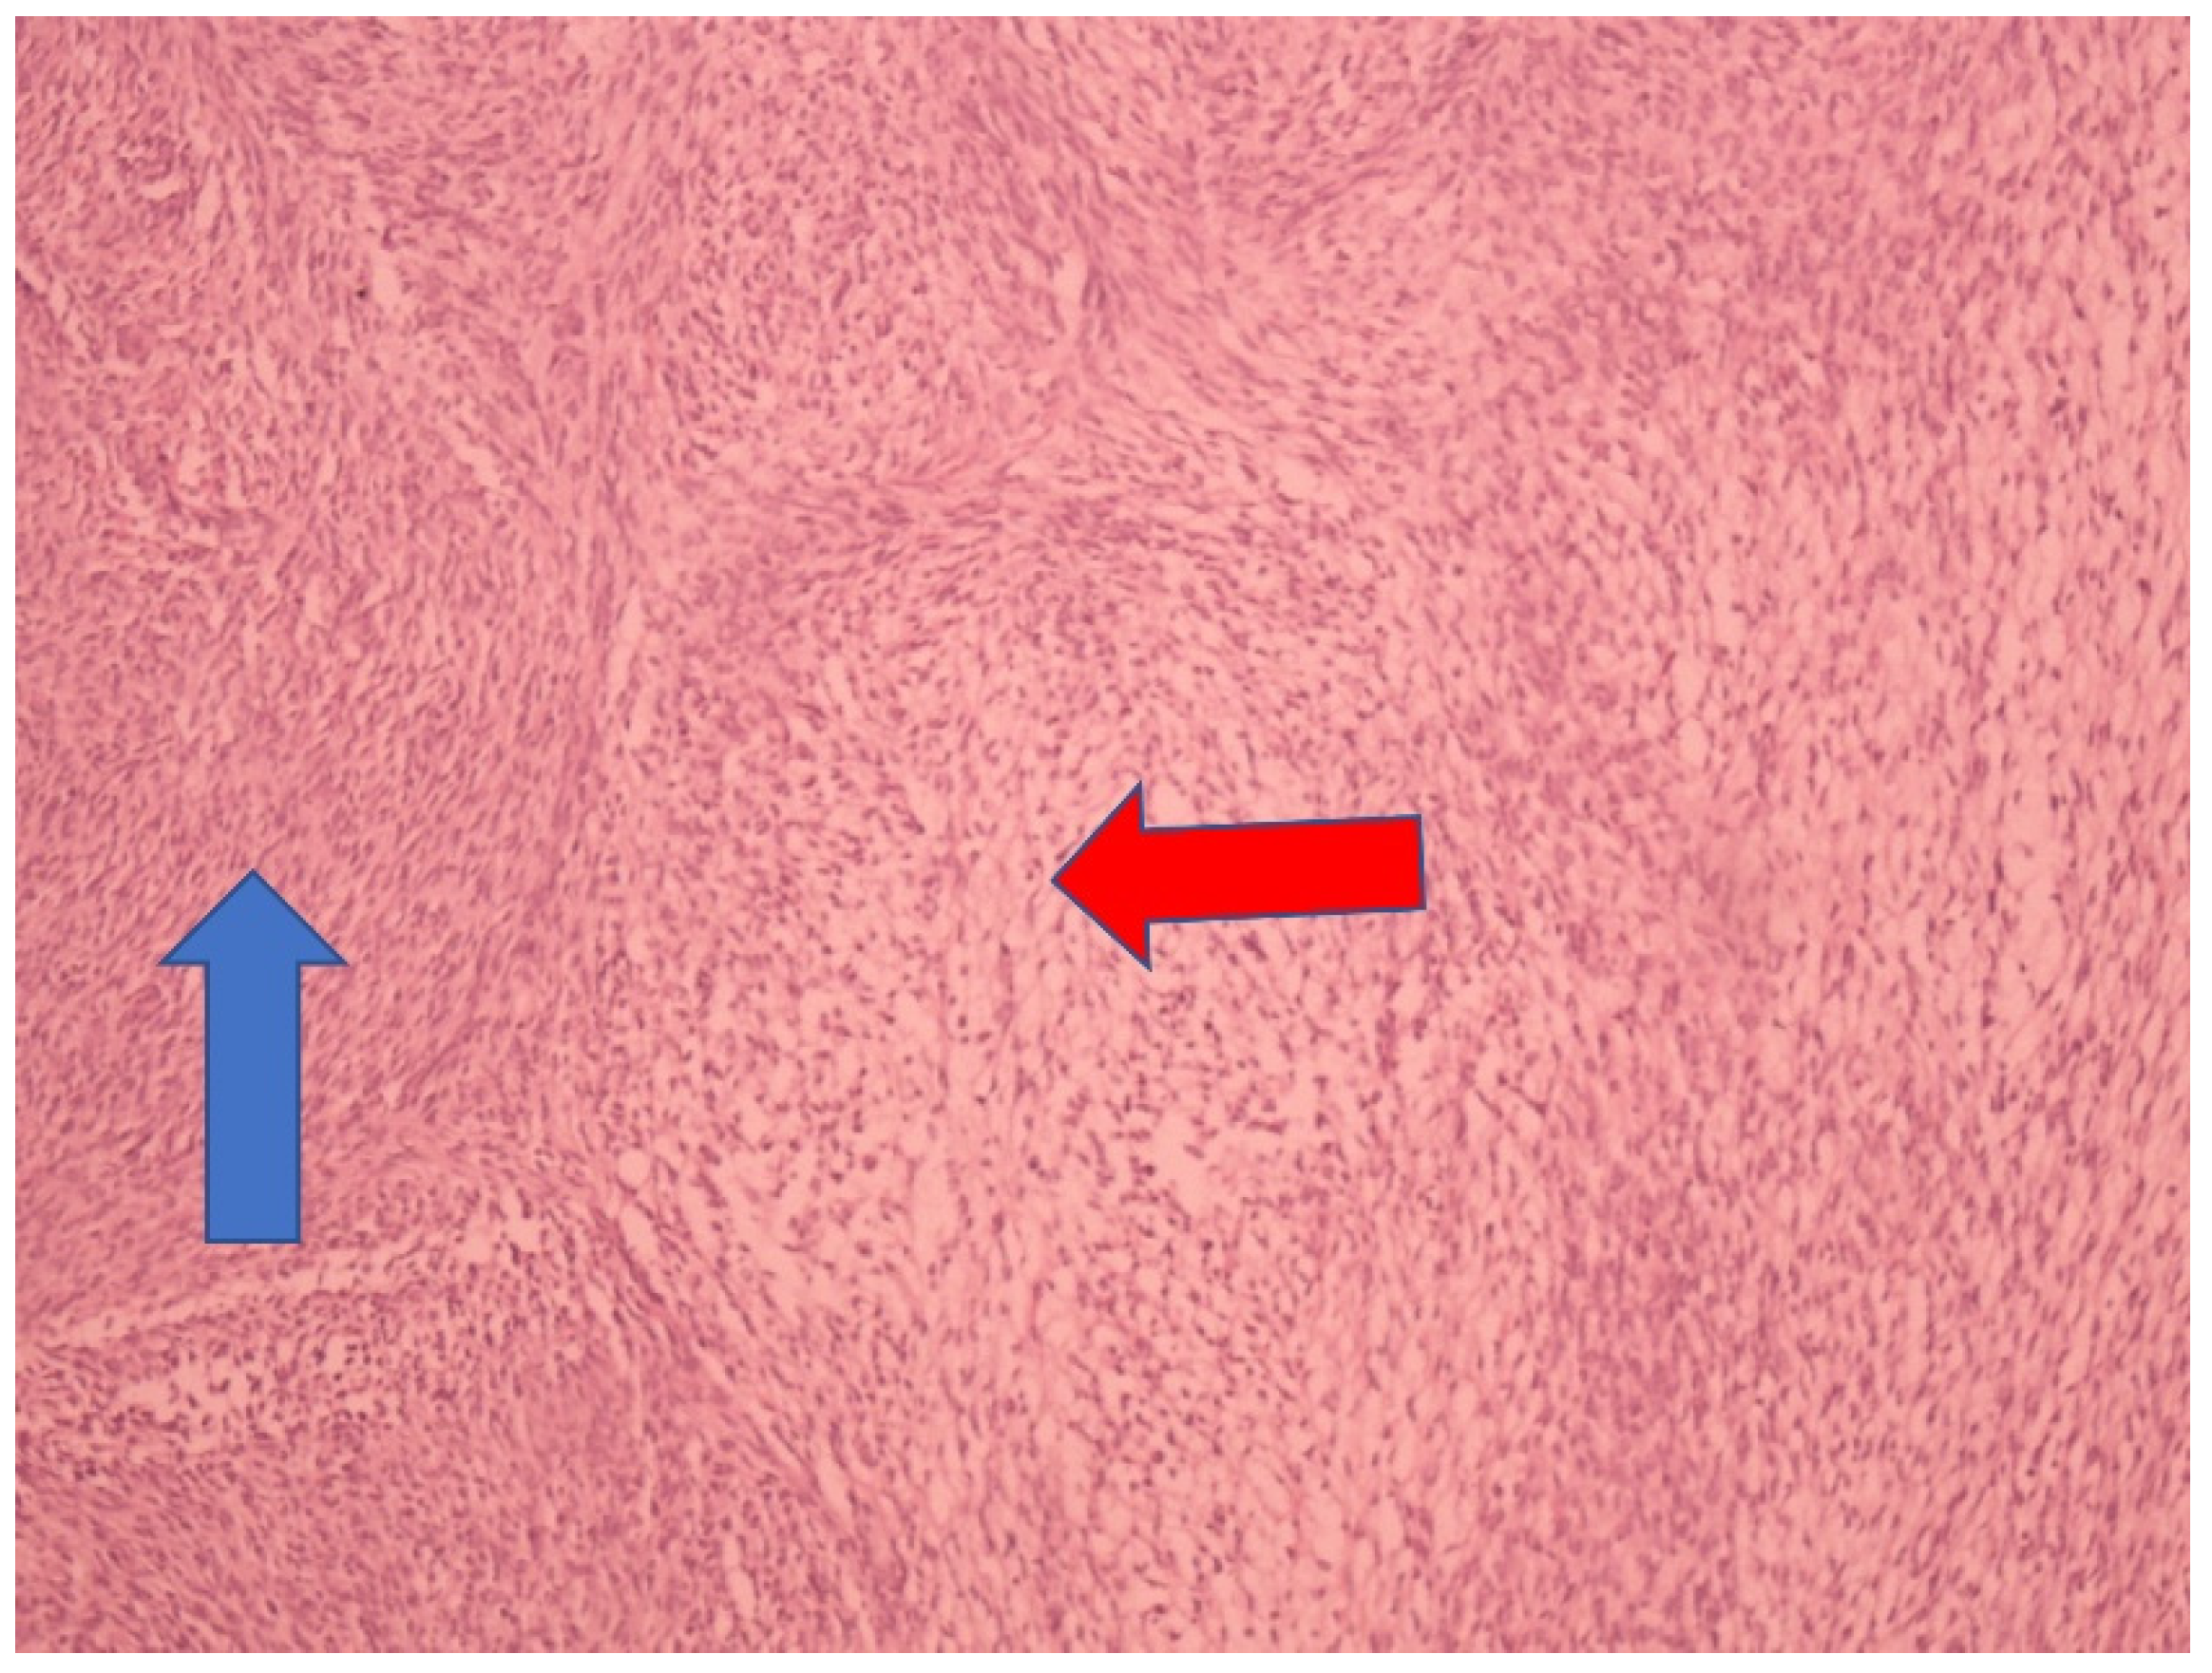

The tumor samples were formalin-fixed, paraffin-embedded, and stained with hematoxylin/eosin (HE). Immunohistochemistry (IHC) staining was performed using Vimentin (Ventana (V9) Mouse monoclonal antibody), Actin, Muscle specific (Ventana (HHF35), Mouse monoclonal antibody), and Inhibin (Ventana (alpha (R1), Mouse monoclonal antibody). A section 4 mm thick from the paraffin-embedded block was cut, and fully automatized immunoassays were performed on a Ventana BenchMark GX autostainer (Roche, Tucson, AZ, USA). The microscopic analysis revealed that the tumor nodule contains bundles of spindle-shaped, uniform cells. The cells were medium-sized, oval, and mitotically inactive. Subgroups of tumor cells were observed to have a more abundant and light cytoplasm that was spindle- to oval-shaped. Between the bundles of tumor cells, moderate amounts of collagen fibers were present (Figure 3).

Figure 3. Microscopic appearance under HE staining (100×, spindle-shaped tumor cell—blue arrow, oval to round tumor cells—red arrow).